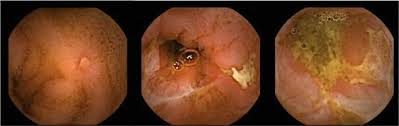

• 내시경 소견

• 종주성 궤양 (Longitudinal ulcer): 4-5cm 이상 길이의 궤양이 장의 주행과 평행한 방향으로 관찰

• 조약돌 점막 모양 (cobblestone appearance): 궤양들이 사방으로 연결되어 심한 궤양들 사이에 남은 점막들이 과형성 및 부종 변화로 돌출되어 조약돌을 깔아놓은 양상으로 관찰. 매우 특징적인 소견

• 아프타성 궤양: 크론병 초기에 나타나는 특징으로, 베체트장염/장결핵 등 다른 질환과의 감별 필요